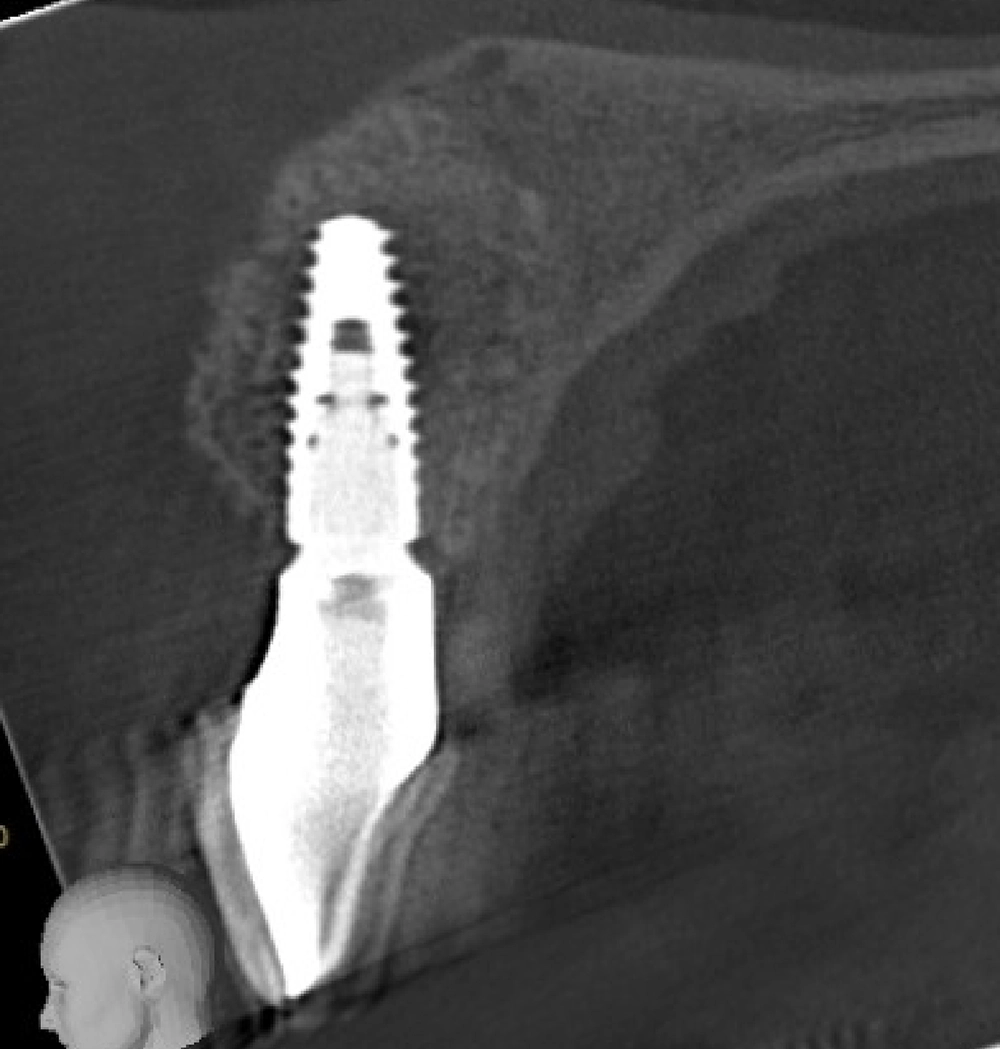

Hard Tissue Augmentation

Restores lost bone in areas where dental implants are planned. Bone grafts—either natural or synthetic—are used to rebuild the alveolar bone for strength and stability

Hard tissue augmentation 3 (b)